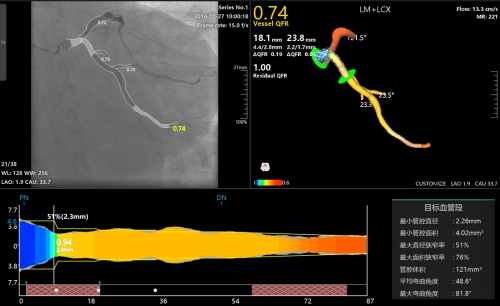

新一代AI QFR测量系统界面更简洁,操作更智能、计算更精准

据心内科朱虹岷博士介绍,QFR是基于冠脉造影影像的无导丝FFR快速分析系统,第一代QFR测量基于两幅角度差大于25°的常规冠脉血管造影图像进行血管重建与血流分析,从而获得血流储备分数。新一代的AI QFR技术较前一代技术有很大改进,首先,在基于第一代QFR同源核心算法的基础上加入了人工智能算法,例如血流速度的计算,感兴趣血管段的选择,管腔轮廓勾画,分支计算等都融入了人工智能算法,大大简化了个人操作流程,也减少了个人操作误差,从而使得计算更精准,时间也更短;其次,新一代AI QFR可分别完成2D-QFR和3D-QFR测量,对于冠脉造影暴露清晰的病变,只需要一幅造影图像,在30秒内就能完成2D-QFR分析,计算精度超过93%;对于复杂病变可进行3D-QFR分析,需结合2个体位造影图像,1分钟左右即可完成分析,由于人工智能的辅助,因此较前一代QFR计算更准确;第三,基于造影的人工智能辅助全自动冠脉树无创FFR计算,是目前全球独家可进行分叉病变功能学分析的技术;最后,在AI QFR系统中,增加了微循环功能计算,从而完善了全冠脉系统的生理学功能评估。基于上述这些优点,相信未来QFR会有更广阔的应用前景。